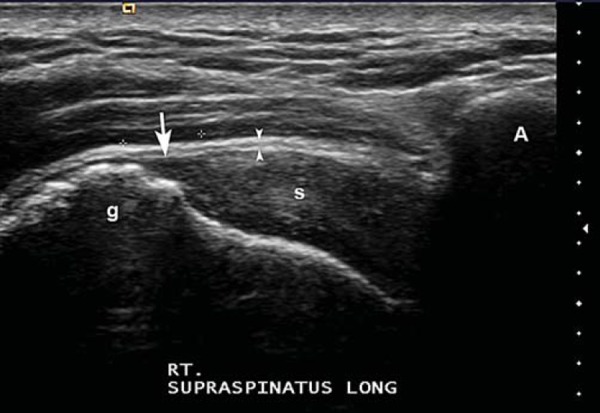

Antes de buscar la patología, tienes que tener clara la imagen normal. En una exploración correctamente realizada, el supraespinoso sano se verá así:

En eje longitudinal (corte largo): el tendón tiene una estructura fibrilar bien definida, hiperecoica, con líneas paralelas y continuas. La corteza ósea del troquíter se ve como una línea blanca y brillante. Por encima del tendón, la bursa subacromial-subdeltoidea aparece como una fina línea hipoecoica (no siempre visible en condiciones normales) y, por encima de esta, el músculo deltoides.

Rotura parcial articular (cara profunda): es la más frecuente. Se produce en la interfase articular del tendón, la que está en contacto con la cabeza humeral.

En roturas de la cara articular, el defecto se sitúa en la interfase profunda del tendón. En las de la cara bursal, en la interfase superficial, lo que puede acompañarse de engrosamiento de la bursa o líquido